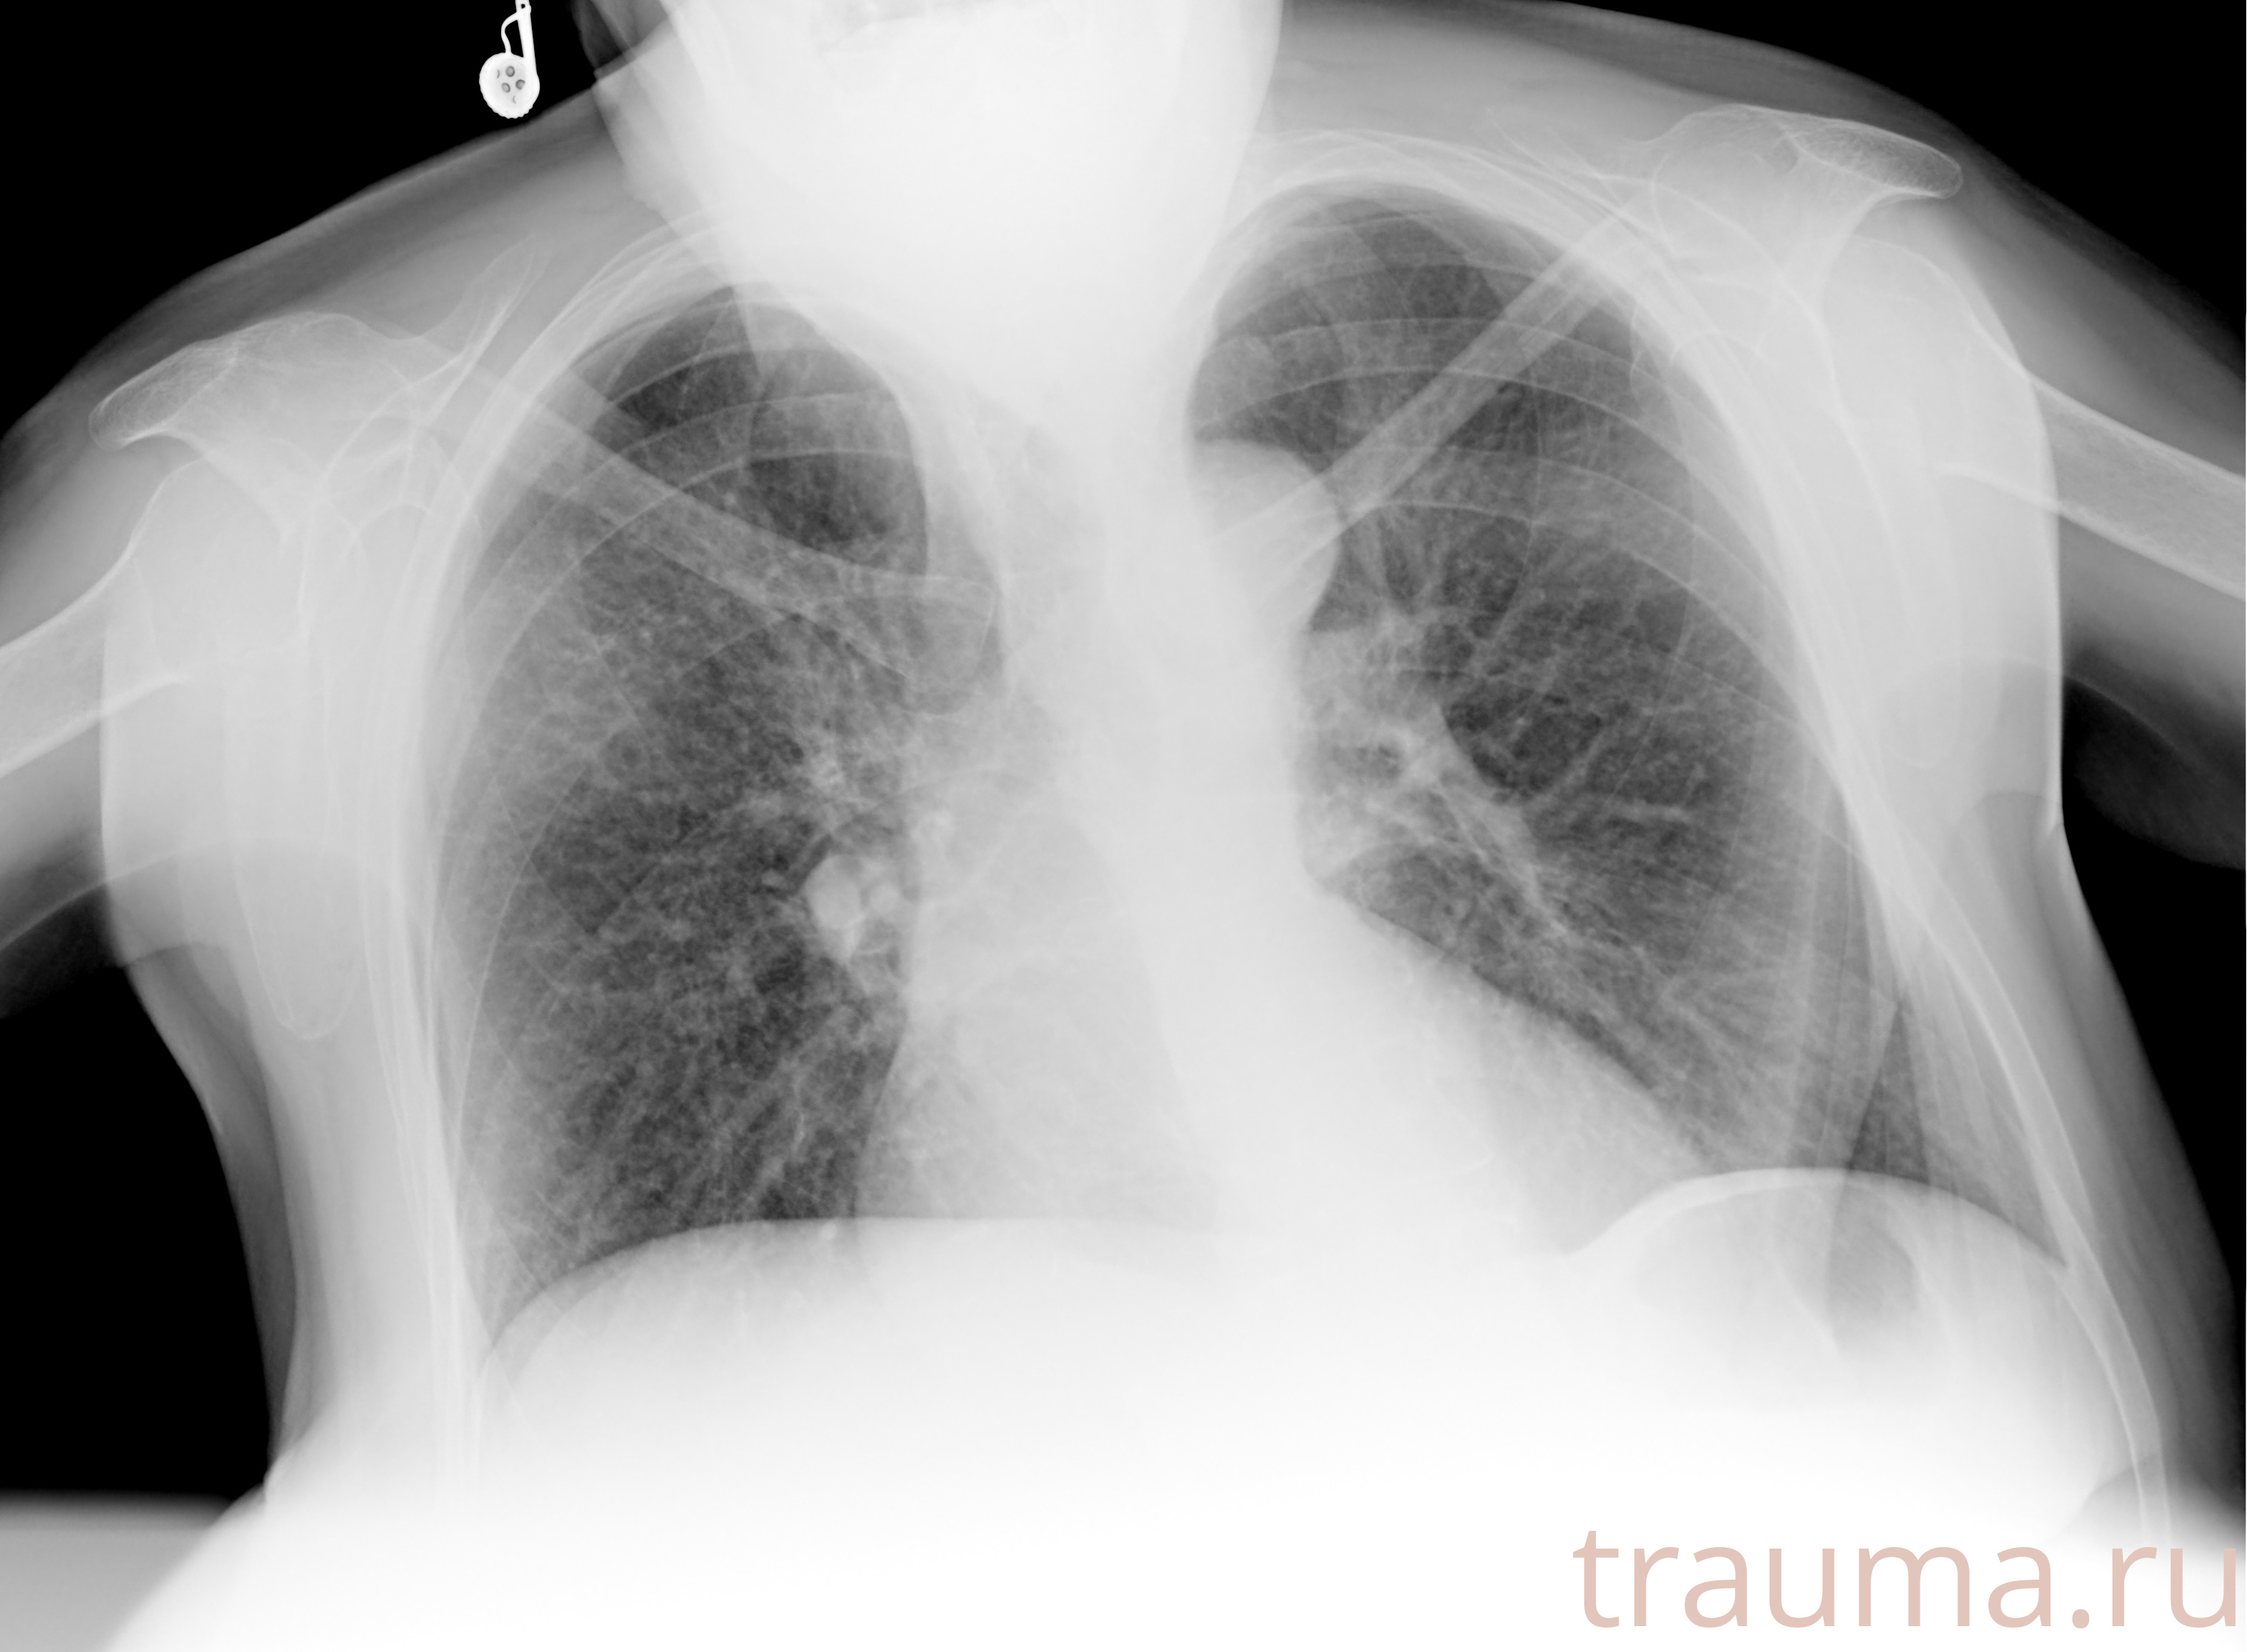

Рентгенограммы

Рентген на дому: по вашему адресу приезжает врач-рентгенолог, травматолог-ортопед с мобильным рентгеновским аппаратом, проводит диагностику травмы или заболевания, делает необходимые рентгенограммы, дает рекомендации по дальнейшему лечению. Получить качественные снимки в домашних условиях возможно благодаря уникальной методике, разработанной МосРентген Центром для института  Склифосовского

при переломе шейки бедра и пневмонии от компании МосРентген Центр - партнера Института имени Склифосовского